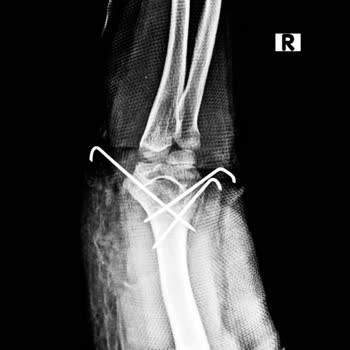

Zeytinburnu'daki Koç Üniversitesi acil bölümüne 03.10.2024 tarihinde kızım z. D**. Ş. Sol ayak bileğinde bileğinde şiddetli ağrıyla acil bölümüne götürdüm. Acilde röntgen çekildi. Sol ayağında olmasına rağmen 2 ayağını da röntgen çekilmiş olduğunu gördük. Acil de ayağında kırık olmadığı ortopedi dok...